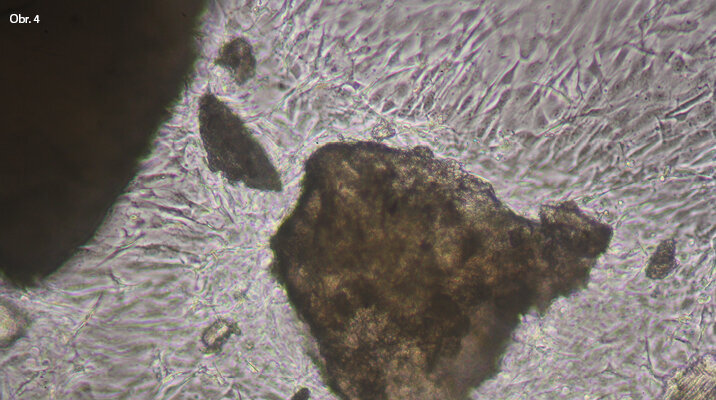

Rozemletá tvrdá zubní tkáň ve zkouškách in vitro s buňkami MG63. Je vidět afinita buněk k některým zrnům tvrdé zubní tkáně.

Afinita k zrnům tvrdé zubní tkáně je vidět na zrnu, které je obaleno buňkami. Předpokládáme, že toto zrno je dentin. Velké zrno v pravé části obrazu je bez buněčného obalu. Předpokládáme, že jde o sklovinu.

Mezi zrny tvrdé zubní tkáně se poměrně rychle (cca do 24 hodin) vytváří ucelený buněčný můstek, což může znamenat rychlou tkáňovou reakci